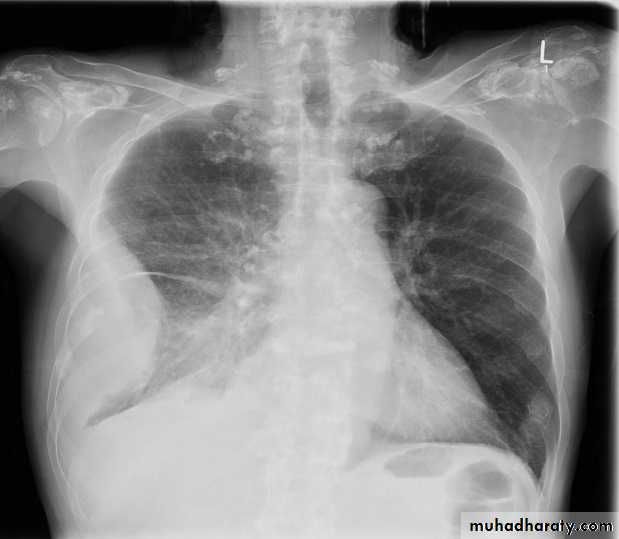

TB of the lung

Tuberculosis encompasses an enormously wide disease spectrum affecting multiple organs and body systems predominantly caused by the organism Mycobacterium tuberculosisPulmonary manifestations of tuberculosis are varied and depend in part whether the infection is primary or post-primary. The lungs are the most common site of primary infection by tuberculosis and are a major source of spread of the disease .

Post primary TB radiographic appearance

Post-primary pulmonary tuberculosis, also known as reactivation tuberculosis or secondary tuberculosis occurs years later, frequently in the setting of a decreased immune status. In the majority of cases, post-primary TB within the lungs develops in either :

* posterior segments of the upper lobes

*superior segments of the lower lobes

Typical appearance of post-primary TB

1.patchy consolidation or poorly defined linear and nodular opacities in both apices , upper zone in one lung , & lower zone in other lung ( ulternating lesion ) .2. Post-primary infections are far more likely to cavitate with multiple abscess formation & air fluid level more develop in the posterior segments of the upper lobes.

3. Tuberculomas seen in post-primary TB and appear as a well defined rounded mass typically located in the upper lobes .

4. Miliary tuberculosis is uncommon but carries a poor prognosis. It represents haematogenous dissemination of an uncontrolled tuberculous infection. It is seen both in primary and post-primary tuberculosis. Although implants are seen throughout the body, the lungs are usually the easiest location to the image. Miliary deposits appear as 1-3 mm diameter nodules . are uniform in size and uniformly distributed